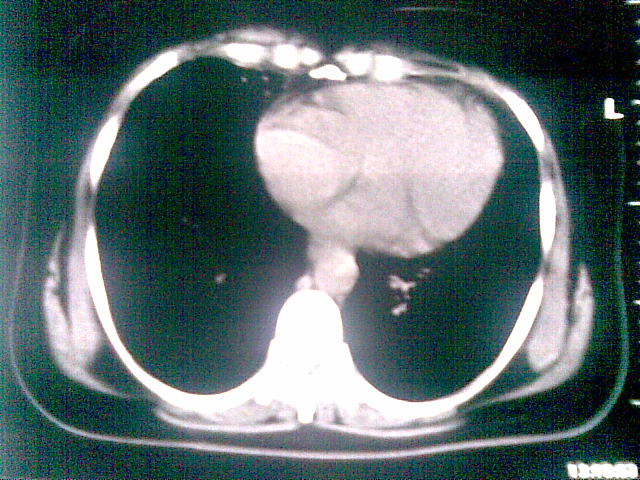

两上肺均见有斑片条结及蜂窝状环状低密度影,以右侧居多,考虑肺结核并支扩可能。

支扩并感染,结核不能排除,建议结合实验室检查或痰检。